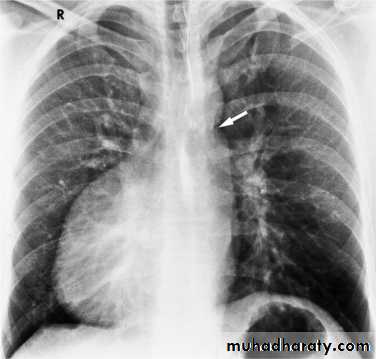

Hila

Left hilum is higher than theRt in 97%

Both hila should be equal density & size with concave lateral borders

Upper limbs of hila ( superior pulmonary veins)Lower limbs of hila ( inferior

pulmonary arteries )

Normal LNs not visible at CXR

Hilar enlargement ( Bilateral )

1) Expiratory film2)LAP –hematological malignancy(leukemia, lymphoma ..)

-infections ( whooping cough or TB ?)

3) Vascular causes

Hilar enlargement ( unilateral )

1)Apparent –rotation-scoliosis

2) LAP